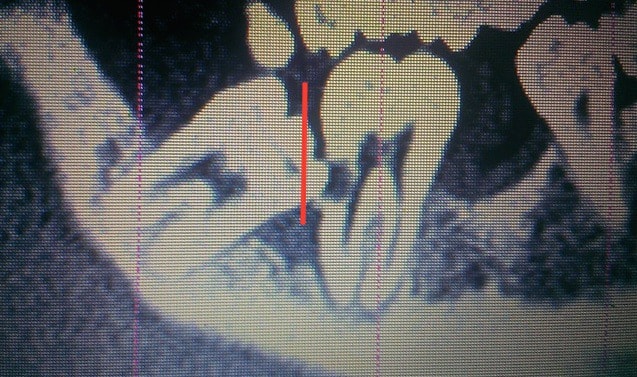

Voici le scanner d'un patient chez qui l'extraction des dents 47 et 48 est indiquée. Etant donné le positionnement de ces dents par rapport au nerf, j'aurais aimé avoir vos différents points de vue quant à la meilleure solution thérapeutique à adopter.

Je te conseillerais de commencer par sectionner la 48 comme je l'ai tracé sur l'image jointe.

La 48 semble s'emboîter dans la carie distale de 47 et risque de la bloquer. Ensuite je tenterais de les mobiliser avant de décider la séparation des racines.